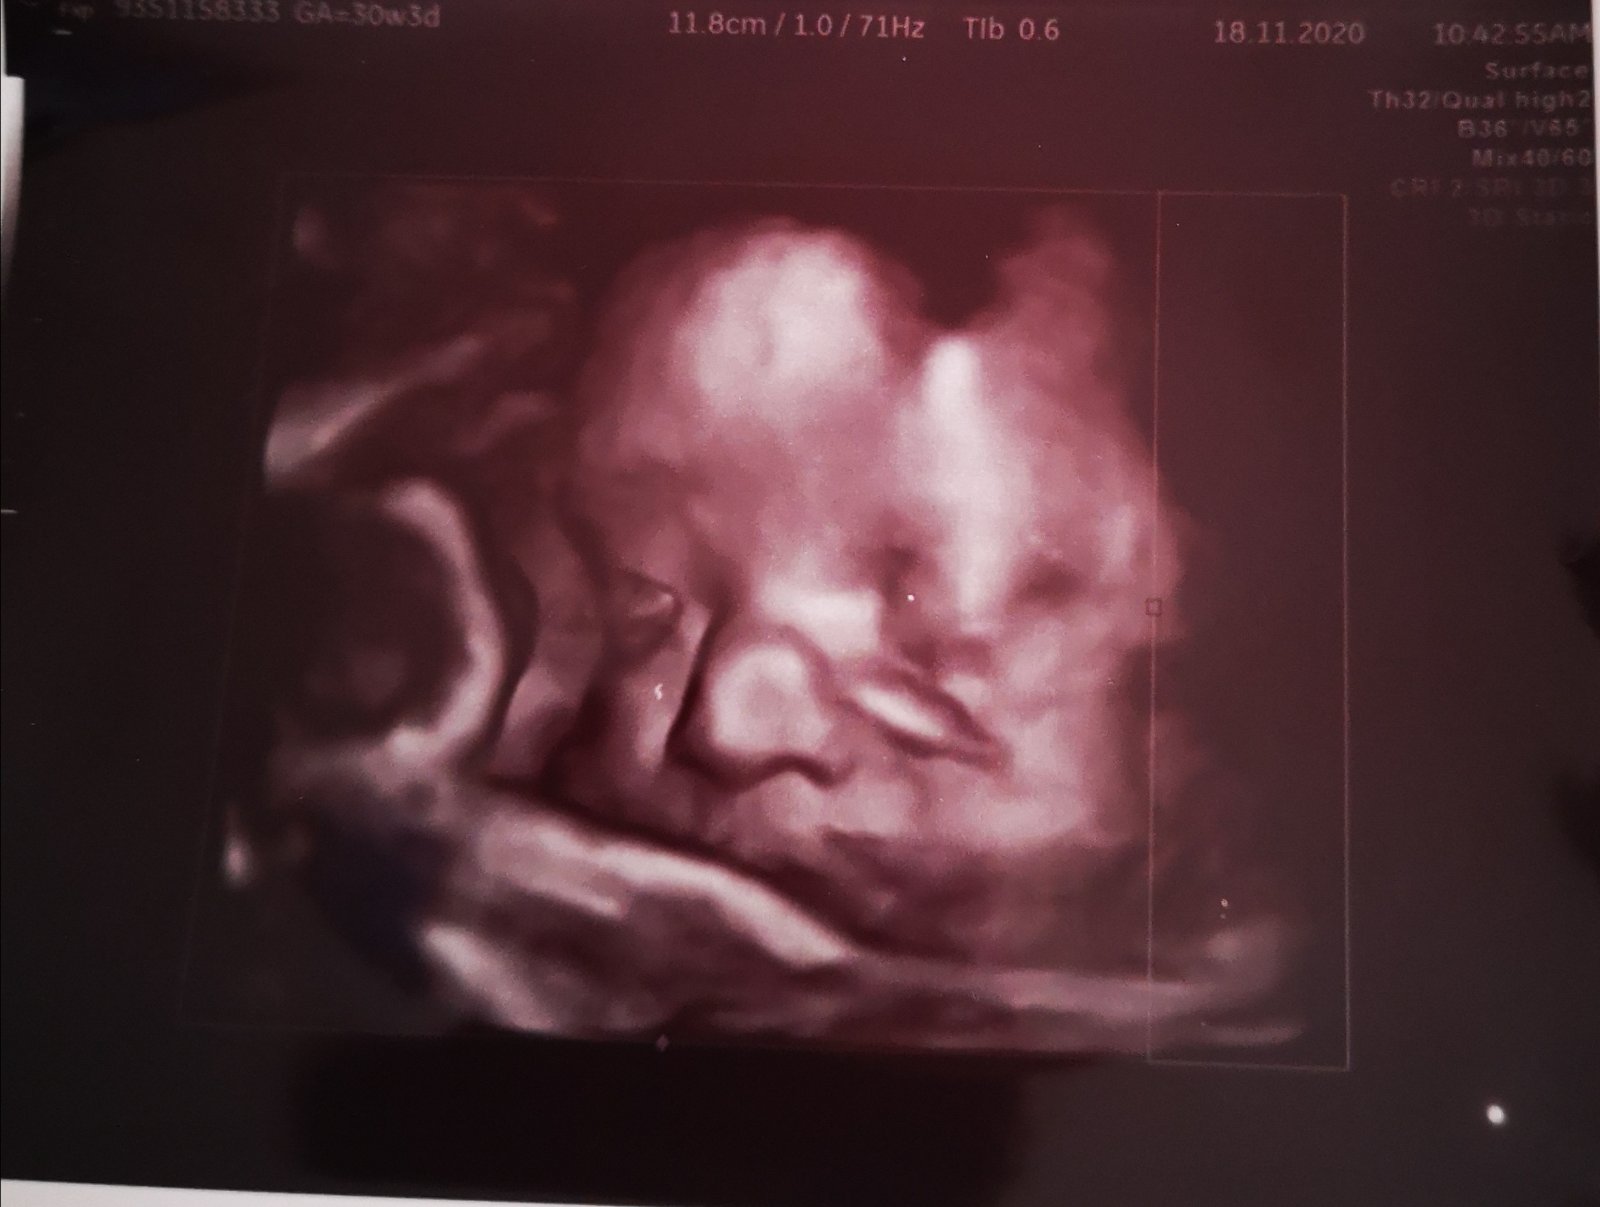

Ahojte baby som v 31 tyzdni uz ked som bola v 20 tyzdni mi doktorka pri sone povedala ze male ma mensi noztek vtedy namerane 5,1 ale inak vsetky ostatne minor markery negativne.. V 26 tyzdni povedala ze to nic neznamena ze moze mat mensi noztek a kedze sa mali tocil tak ze sa to neda presne ani odmerat.. A teraz v 31 tyzdni vravela ze no na lavo je hypoplazia nosovej ale to nemusi vobec nic znamenat.. Tak sa pytam ci stym mate skusenosti a ci bolo vsetko v poriadku

@visna6 tak mne povedali ze mam na lavo hypollaziu tej nosovej a doktor nameral v 20 tyzdni 5,1 a napisal zaver ze minor markery negativne az na nb.. A teraz doktorka ze no je to tam ale nemusi to nic znamenat.. V 12 tyzdni sme mali nt hranicne ale nakoniec krv dopadla dobre tak doktorka nechcela aby som sla na odber plodove